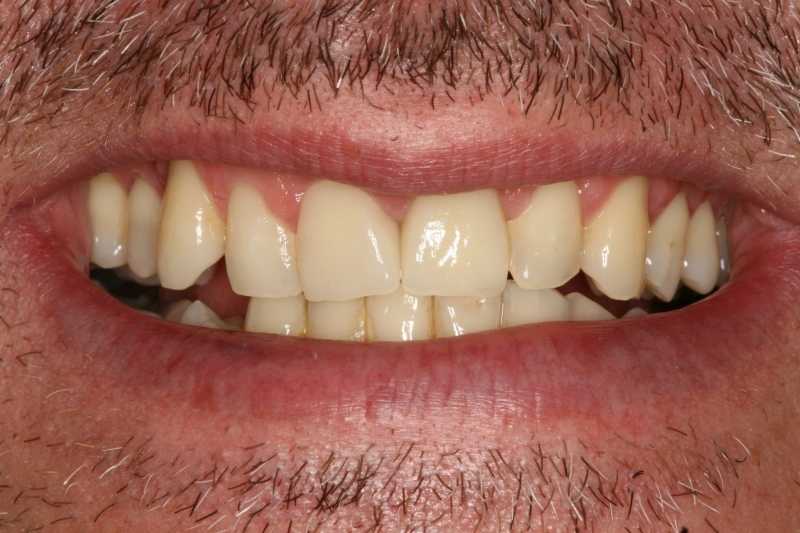

45 éves férfipáciensünk a képen látható státusszal érkezett klinikánkra: letört és nem korrekt gyökértöméssel rendelkező bal felső nagymetszővel, ill. régi, elszíneződött töméssel bíró, formáját tekintve kedvezőtlen esztétikájú jobb felső nagymetsző foggal.

Kiindulási állapot